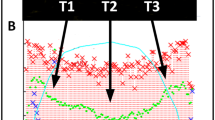

The most frequently used tool for mitral regurgitation (MR) quantification in clinical practice is “eyeballing” of the colour flow jet area to differentiate between mild and severe MR [1]. This practice is primarily explained by its ease of use. However, it seems inadequate to solely use a qualitative diagnostic parameter to distinguish between mild, moderate, and severe MR [2,3,4,5]. As mentioned in recent recommendations, “eyeballing” of the MR jet area is misleading [3, 5, 6]. This is caused by its variations depending on ultrasound settings (Fig. 1), the different display of the jet area in respective sectional planes, and the haemodynamic variations influencing MR dynamics. In consequence, recent papers had eliminated this method in the respective tables [6, 7]. The key point statements—“The colour flow area of regurgitant jet is not recommended to quantify the severity of MR. The colour flow imaging should only be used for diagnosing MR. A more quantitative approach is required when more than a small central MR jet is observed” [3]—emphasize the necessity of a definite quantitative approach for grading MR severity.

The methodological factors influencing color-coded flow phenomena (PISA, VC, jet area)—illustrated by optimal colour Doppler settings with 1.8 MHz Doppler frequency, increased Doppler sample volume, reduced low-velocity reject, increased frame rate, increased Doppler frequency with 3.1 and 3.6 MHz, increased colour pixel smoothing, reduced colour scale, reduced and increased 2D gain, reduced and increased colour gain, reduced and increased 2D priority, and reduced and increased zero line shift